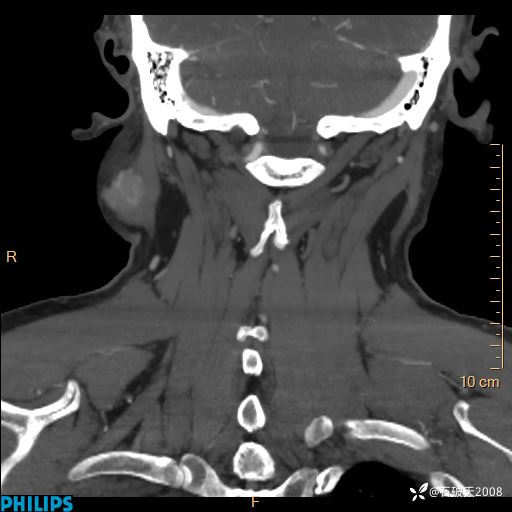

病例分享:颈部占位,一周后公布病理

男 57岁 主 诉:发现右侧颌下肿物1月余。

现病史:1月余前家属发现右侧颌下肿物。局部皮肤无红肿、热痛,无吞咽困难,无异物感,无恶心、呕吐,无头痛、头晕,无胸闷、胸痛,无发热、咳嗽、咳痰及呼吸困难。于我院行体表肿块彩超检查(2024.03.15我院)示:右侧耳下皮下软组织内低回声,未治疗。今为进一步治疗门诊以“腮腺肿瘤”为诊断收住我科,发病来患者神志清,精神可,饮食、睡眠及大小便正常,体重无明显下降。

静脉期